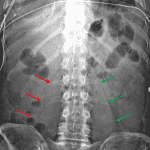

- Nonobstructive bowel gas pattern

- Obscuring of the right psoas shadow

- Hazy bibasilar pulmonary opacities

- Right-sided calcified pleural plaque

- Central venous catheter tip overlying the superior cavoatrial junction

- Retroperitoneal hematoma

Nonobstructive bowel gas pattern.

Obscuring of the right psoas shadow, which raises concern for an adjacent mass or hematoma. Recommend CT for further evaluation.

Hazy bibasilar pulmonary opacities, which could be further evaluated with dedicated chest radiographs.